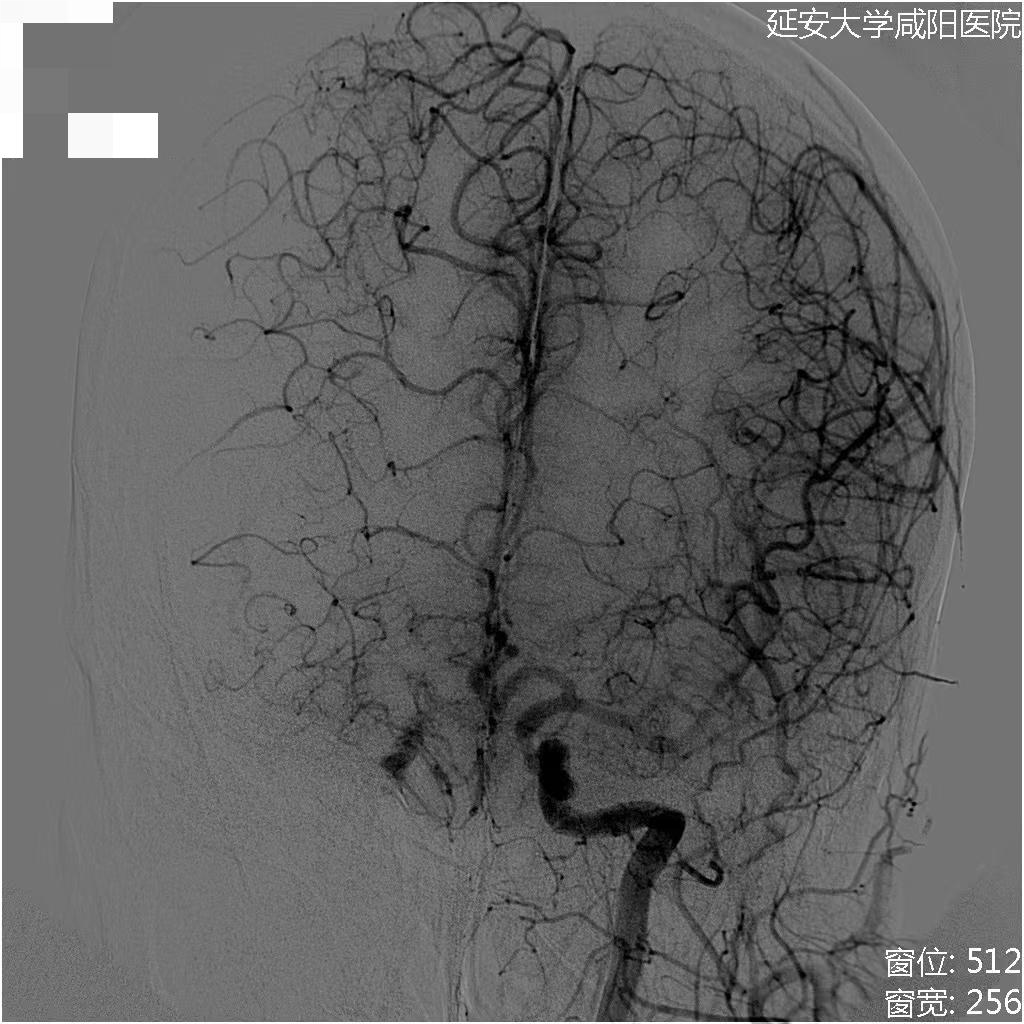

初始造影RICA起始位

病历夹什么径技·第152期|串联营病历夹:川陕大营_https://www.jmylbn.com_新闻资讯_第81张

初始造影后循环+LICA正位

病历夹什么径技·第152期|串联营病历夹:川陕大营_https://www.jmylbn.com_新闻资讯_第82张

过程影像

病历夹什么径技·第152期|串联营病历夹:川陕大营_https://www.jmylbn.com_新闻资讯_第83张

病历夹什么径技·第152期|串联营病历夹:川陕大营_https://www.jmylbn.com_新闻资讯_第84张

<<滑动查看下一张图片>>

病历夹什么径技·第152期|串联营病历夹:川陕大营_https://www.jmylbn.com_新闻资讯_第85张

病历夹什么径技·第152期|串联营病历夹:川陕大营_https://www.jmylbn.com_新闻资讯_第86张

病历夹什么径技·第152期|串联营病历夹:川陕大营_https://www.jmylbn.com_新闻资讯_第87张

对侧造影显示,右侧大脑前动脉供血区血流较好。

病历夹什么径技·第152期|串联营病历夹:川陕大营_https://www.jmylbn.com_新闻资讯_第88张

接下来处理远端,Synchro微导丝与Rebar微导管的辅助下,选择置入Solitaire(4-20)支架,支架打开后使用抽拉结合的方式使血管再通。

病历夹什么径技·第152期|串联营病历夹:川陕大营_https://www.jmylbn.com_新闻资讯_第89张

取栓后造影如下:

手术评估

病历夹什么径技·第152期|串联营病历夹:川陕大营_https://www.jmylbn.com_新闻资讯_第90张

病历夹什么径技·第152期|串联营病历夹:川陕大营_https://www.jmylbn.com_新闻资讯_第91张

病历夹什么径技·第152期|串联营病历夹:川陕大营_https://www.jmylbn.com_新闻资讯_第92张